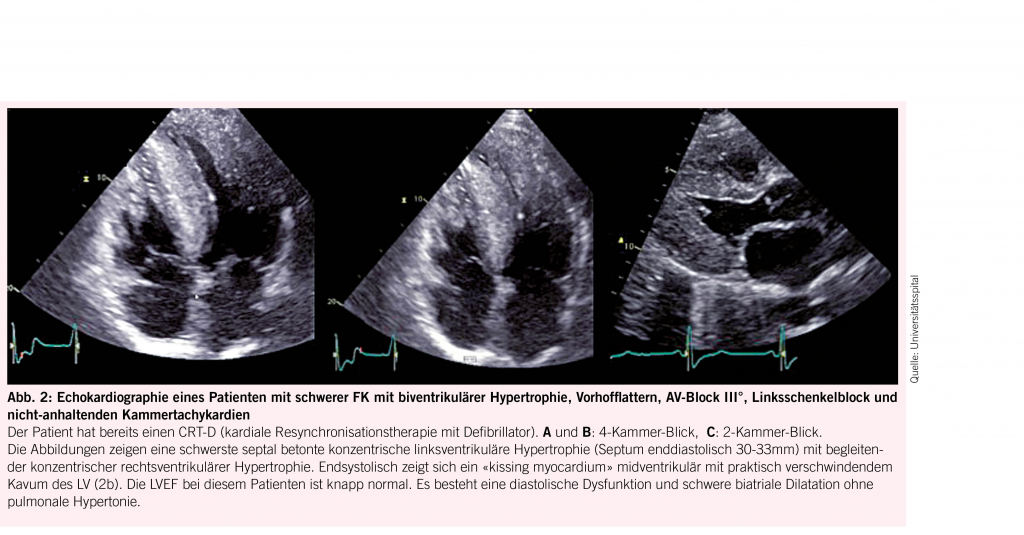

Das Herz ist mit 68% das Organ mit der häufigsten intrazellulären GB3-Akkumulation (10,11), die in den Myozyten, Herzklappen und Gefässendothelien stattfindet und neben der Infiltration auch einen inflammatorischen und oxidativen Stress verursacht (12). Als Folge leiden über die Hälfte der männlichen Fabry-Patienten und 18- 28% der Frauen mit Morbus Fabry (13, 14) unter einer konzentrischen LVH (siehe Abb. 2) mit einer typischerweise früh einsetzenden diastolischen Dysfunktion (15,16) und im Verlauf restriktivem Füllungsmuster (17, 18). Die LVH bei Fabry unterscheidet sich in der Regel durch das Fehlen einer Ausflussobstruktion von einer idiopathischen hypertrophischen Kardiomyopathie (4) und kann auch mit einer rechtsventrikulären Hypertrophie und Dysfunktion einhergehen (19). Während bei Männern erste kardiale Beschwerden mit durchschnittlich 33 Jahren einsetzen, wurde bei Frauen ein späterer Beginn um das 40. Lebensjahr beobachtet (7). Typischerweise kommt es im Verlauf zu einer Herzinsuffizienz mit erhaltener Ejektionsfraktion (7). Aufgrund der Endothelablagerungen kann es zudem oft auch zu einer endothelialen Dysfunktion (20, 21) kommen. Möglich ist auch eine mikrovaskuläre Dysfunktion, die Angina pectoris verursacht (22). Die fortgeschrittene Fabry-Kardiomyopathie (FK) ist durch eine fibrotische Umwandlung des linken Ventrikels, die typischerweise infero-baso-lateral beginnt und nach transmural fortschreitet, gekennzeichnet (23). Diese Fi-broseareale können Rhythmusstörungen (siehe Abb. 3), darunter Sinusbradykardien, höhergradige AV-Blockierungen, und Kammertachykardien hervorrufen und infolge zum plötzlichen Herztod führen (24-26). Auch Vorhofflimmern ist bei Fabry-Patienten häufig zu finden, wobei die Inzidenz vier Mal so hoch ist wie in der Normalbevölkerung, bei über 50-jährigen Patienten sogar zwölffach erhöht (25). Bei der fortgeschrittenen FK kommt es gelegentlich auch zur Herzklappenschädigung, insbesondere zur Insuffizienz der Aorten-, Mitral- oder Trikuspidalklappe (24) sowie Erweiterung der Aortenwurzel (27). Eine weitere typische Veränderung ist ein prominenter Papillarmuskel (28) (Abb. 2).

Die transthorakale Echokardiografie ist die primäre und am leichtesten verfügbare Methode zum Screening und zur Verlaufsbeurteilung bei FK (Abb. 2). Sie ermöglicht es jedoch nicht, eine Fabrykardiomyopathie von anderen Hypertrophien abzugrenzen und eine Herzbeteiligung vor Beginn der LVH zu erkennen. Letzteres ist gerade bei Frauen relevant, da diese eine Myokardfibrose oft noch vor den Zeichen einer LVH entwickeln (29). Insgesamt haben mittlerweile 60% der Patienten bei der Diagnosestellung noch keine nachweisbare LVH (30). Durch den Einsatz neuerer Techniken (z.B. Strain Analyse und 2-D Speckle Tracking) können jedoch myokardiale regionale Unterschiede sowie eine beginnende diastolische Dysfunktion vor der LVH detektiert werden (14, 31). Den Goldstandard für die Beurteilung struktureller Veränderungen bei Morbus Fabry sowie die Feststellung von Myokardfibrosen stellt die kardiale Magnetresonanztomographie (CMR) dar. Sie ermöglicht 1. mittels «Late Gadolinium Enhancement» eine frühzeitige Erfassung von Fibrosearealen (16, 32), was von grosser prognostischer Bedeutung ist, da deren Vorhandensein und Ausmass mit dem Risiko des Auftretens potentiell lebensbedrohlicher Rhythmusstörungen korreliert (33) und bei der Indikationsstellung zur ICD-Implantation helfen kann (34), 2. mittels nativem T1 Mapping mit hoher Spezifität und Sensitivität eine FK von anderen Kardiomyopathien zu differenzieren (sehr niedriger T1 Map Wert) (19, 32, 35), und 3. Verlaufskontrollen des Remodelings unter ERT durchzuführen (10, 36). Bei Kontraindikationen für eine CMR kann die Frage nach einer mikrovaskulären Dysfunktion auch alternativ mittels kardialer Positronen-Emissions-Tomographie untersucht werden (37). Im Ruhe-Elektrokardiogramm (EKG, siehe Abb. 3) lassen sich oft charakteristische Veränderungen wie ein positiver Sokolow-Lyon-Index und präkordiale T-Wellen-Negativierungen sowie gelegentlich auch eine PQ-Zeit-Verkürzung und QTc-Zeit-Verlängerung feststellen (38). Bei allen Patienten mit Symptomen sowie bei bekannter Myokardfibrose sollte regelmässig ein Holter-EKG durchgeführt werden. Bei unauffälligem Holter-EKG und persistierendem Verdacht auf eine seltener auftretende HRST sollte die Implantation eines Event Recorders erwogen werden (39). Als Verlaufsparameter, der mit dem Fibrosegrad und dem Schweregrad der FK korreliert, kann hs-Troponin eingesetzt werden (40).